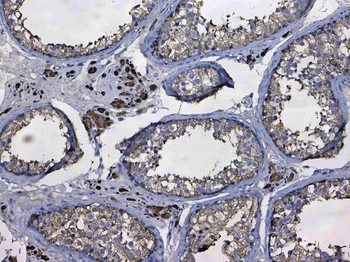

10 μg, 100 μg - Anti-Annexin IV/ANXA4 Antibody [orb18546]

FC, IHC, WB

Human, Mouse, Rat

Rabbit

Polyclonal

Unconjugated

10 μg, 100 μg - Anti-HSPB8/Hsp22 Antibody [orb18992]